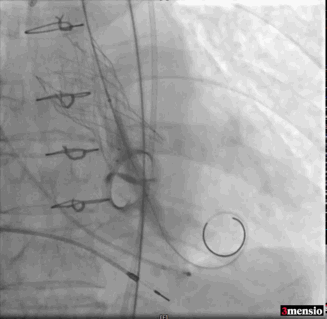

术中导丝跨瓣后20mm球囊预扩,超声判断冠脉风险尚可,植入L23 VenusA Plus可回收瓣膜位置良好,用23mm球囊后扩支架下缘,微少量瓣周漏。

术后即刻血压135/65mmHg,狭窄解除,释放后超声测量瓣下支架长度6mm标准位释放瓣膜位置完美。整台手术用时不足1.5小时,麻醉、超声等团队全程协作为手术顺利完成保驾护航。